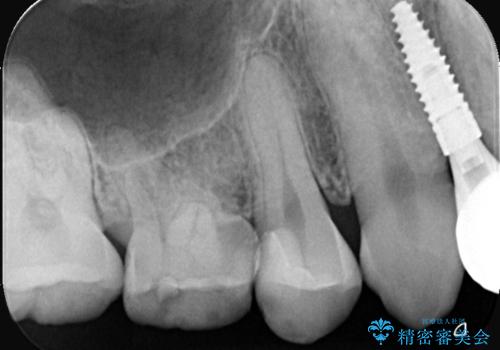

- 「歯がたまに痛む」を主訴に来院された患者様です。 見た目では齲窩が無いように見えますが、レントゲンを撮ると神経の近くまで達する深い虫歯だとわかりました。

虫歯を除去後セラミックインレーで治療を行いました。隣の子どもの歯のEも虫歯になっていたので同時に治療を行いました。

神経の近くまで虫歯が広がっていましたが、神経を保存して治療を行うことが出来ました。

Eに関してはCRで修復を行っています。